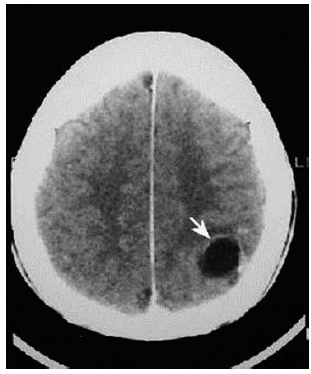

Paciente masculino, 32 anos, previamente hígido, admitido no pronto-socorro com crises convulsivas tônico- clônicas generalizadas. Realizou tomografia de crânio sem contraste em anexo. Assinale a alternativa que apresenta causa mais provável para as crises epilépticas desse paciente.

(https://www.google.com.br/url?sa=i&url=http%3A%2F% 2Fanatpat.unicamp.br%2Fradcisti1.html&psig= AOvVaw3ggRImGRRs2HpnFI_iMY6B&ust= 1627055724801000&source=images&cd=vfe&ved= 0CAsQjRxqFwoTCOiM8YqF9_ECFQAAAAAdAAAAABAD)